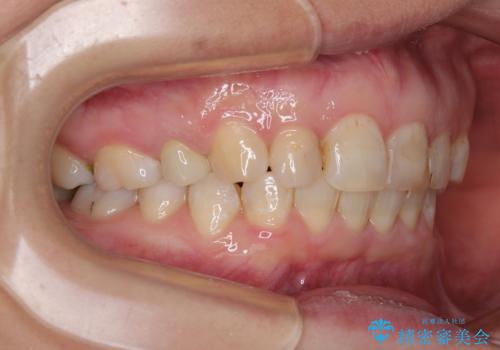

咬合力が非常に強く、スペースがなかなか閉じなかったことと、上下の正中が著しくずれてきてしまったため、下顎左側小臼歯を途中抜歯することとなりました。

歯の動きが鈍く、矯正治療だけで4年以上の期間を要することとなりました。

矯正治療後は、気になっていた銀歯を全てセラミックとし、きれいな口元に仕上げることができました。